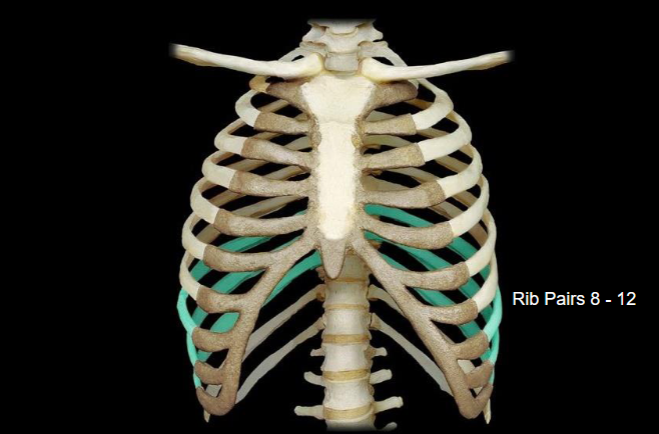

What bone is highlighted in this image?

What type of ribs are highlighted in this image?

vertebronchondral (false) ribs (the 3 ribs right above floating)